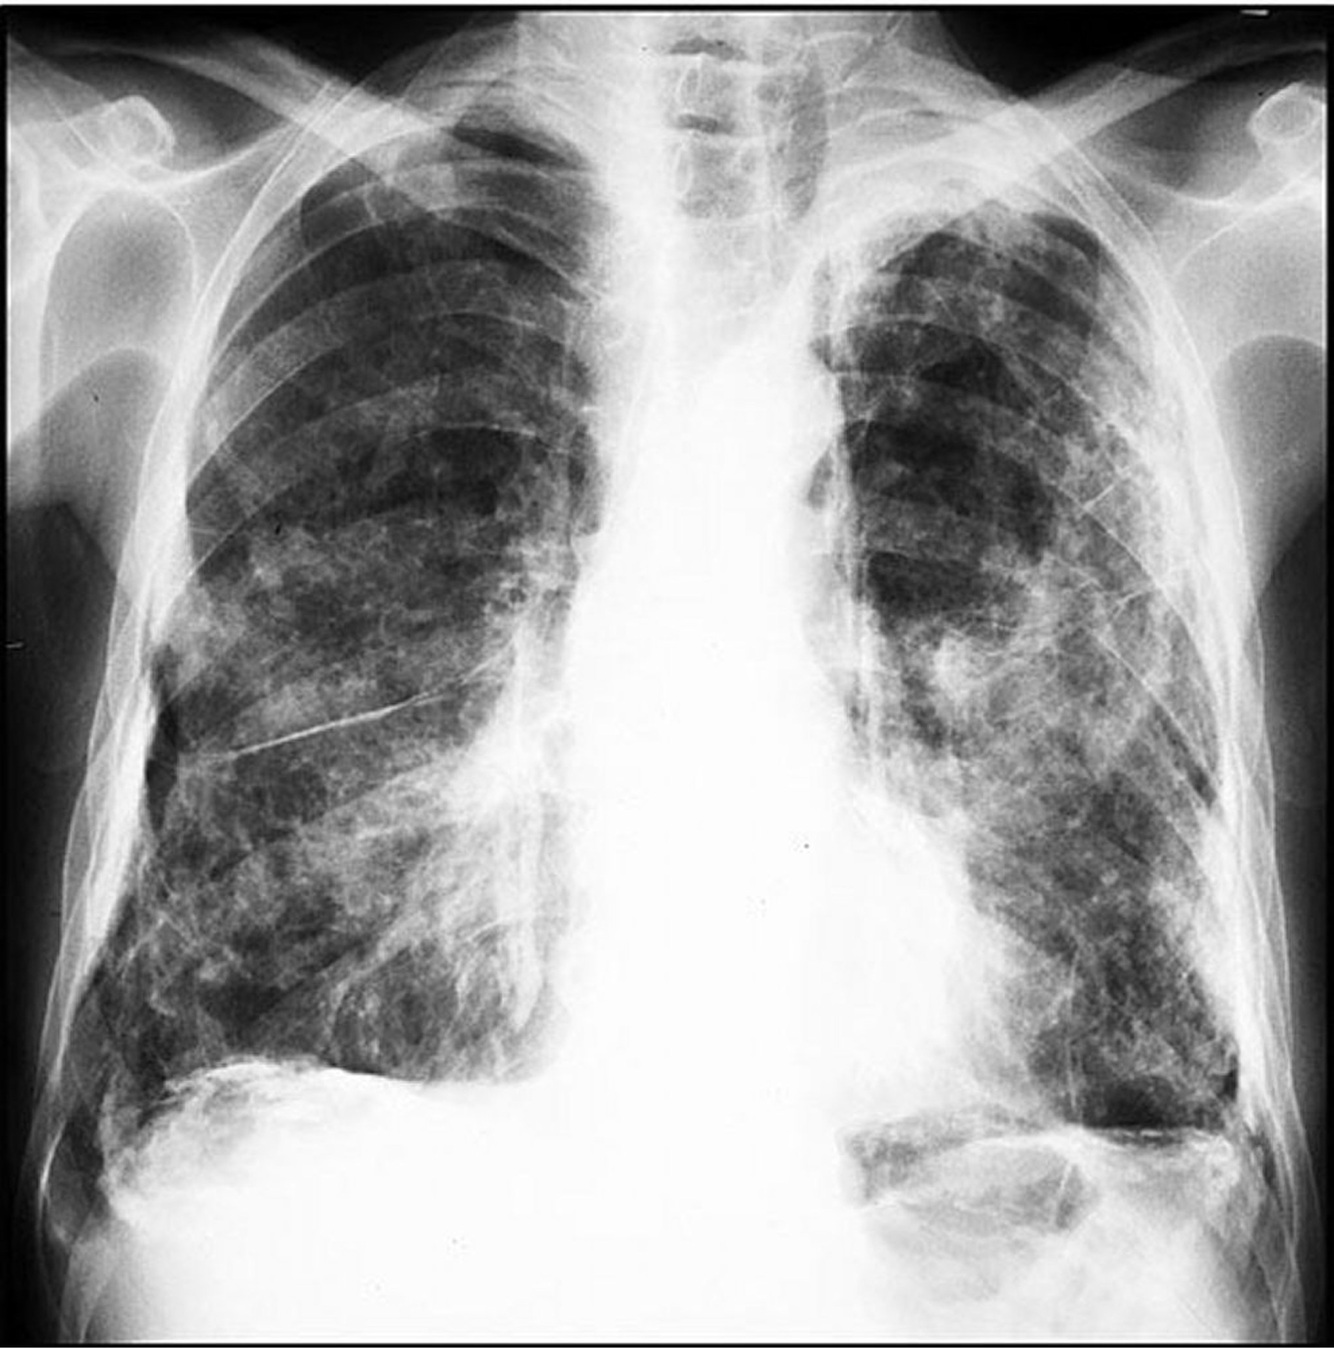

Quais são os achados radiológicos típicos da asbestose na radiografia de tórax?

• Opacidades irregulares ou reticulares, predominando nas bases pulmonares

• Placas pleurais associadas (calcificadas ou não)

• Espessamento pleural difuso, a doença relacionada ao asbesto mais prevalente

• Atelectasia redonda com distorção vascular em cauda de cometa

46

Verdadeiro. ## Footnote A forma simples da doença é caracterizada por pequenas opacidades nodulares (1-5 mm), ocasionalmente associadas a opacidades reticulares ou reticulonodulares, visíveis na radiografia de tórax.

A forma complicada da pneumoconiose dos trabalhadores do carvão é caracterizada por grandes opacidades representando fibrose maciça progressiva, muitas vezes associadas ao enfisema. Verdadeiro ou falso?

Verdadeiro. ## Footnote Na forma complicada, a radiografia pode revelar grandes opacidades devido à fibrose maciça progressiva (FMP), frequentemente acompanhada de enfisema, o que compromete severamente a função pulmonar.